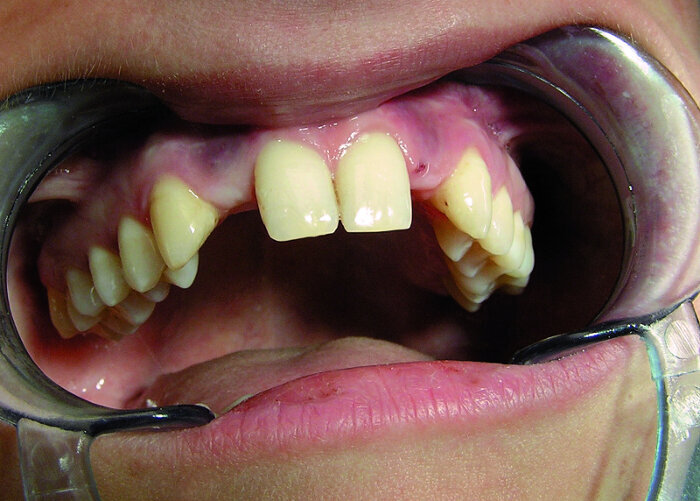

Les incisives latérales symbolisent le tempérament de la personne et ses réactions à l’égard des archétypes ( attitude vis-à-vis des parents ; Fig. 11). Une incisive latérale supérieure droite (dent 12) en vestibuloversion signifie que la personne est capable de défendre sa liberté au sein de la famille, mais elle est généralement en conflit avec le père (Fig. 12). Une position similaire de l’incisive latérale supérieure gauche (dent 22) indique une opposition à la mère (Fig. 13), comme j’en ai eu la confirmation chez les deux patients présentés dans les figures. Si les dents 12 et 22 sont toutes deux en vestibuloversion et chevauchent partiellement les incisives centrales, le patient tend à dominer ses parents.

Par contre, une palatoversion, une microdontie ou une anodontie totale (Fig. 14a) de ces dents est une indication de subordination, souvent dans la famille mais aussi dans la société. Par exemple, la réponse aux questions que je posais à l’enfant de la Figure 14b, chez qui l’on peut observer une occlusion inversée antérieure touchant les incisives latérales temporaires, venait toujours de la mère, sans que l’enfant ne prononce un mot. Par conséquent, un traitement orthodontique, prothétique ou implantaire peut donner à ces patients un bien meilleur départ dans la vie sociétale actuelle (Figs. 15a et b) ainsi qu’une position stable au sein de la famille.